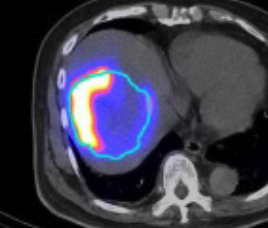

- 釔90選擇性內部放射治療

- 使用鍀99m MAA(左)模擬釔90粒子分佈(右)

- 評估治療可行性

- 由雙示踪劑正電子/電腦雙融掃描計算處方劑量

- 用正電子/電腦雙融掃描顯示釔90粒子分佈(右)

99mTc MAA SPECT/CT Y-90 PET/CT